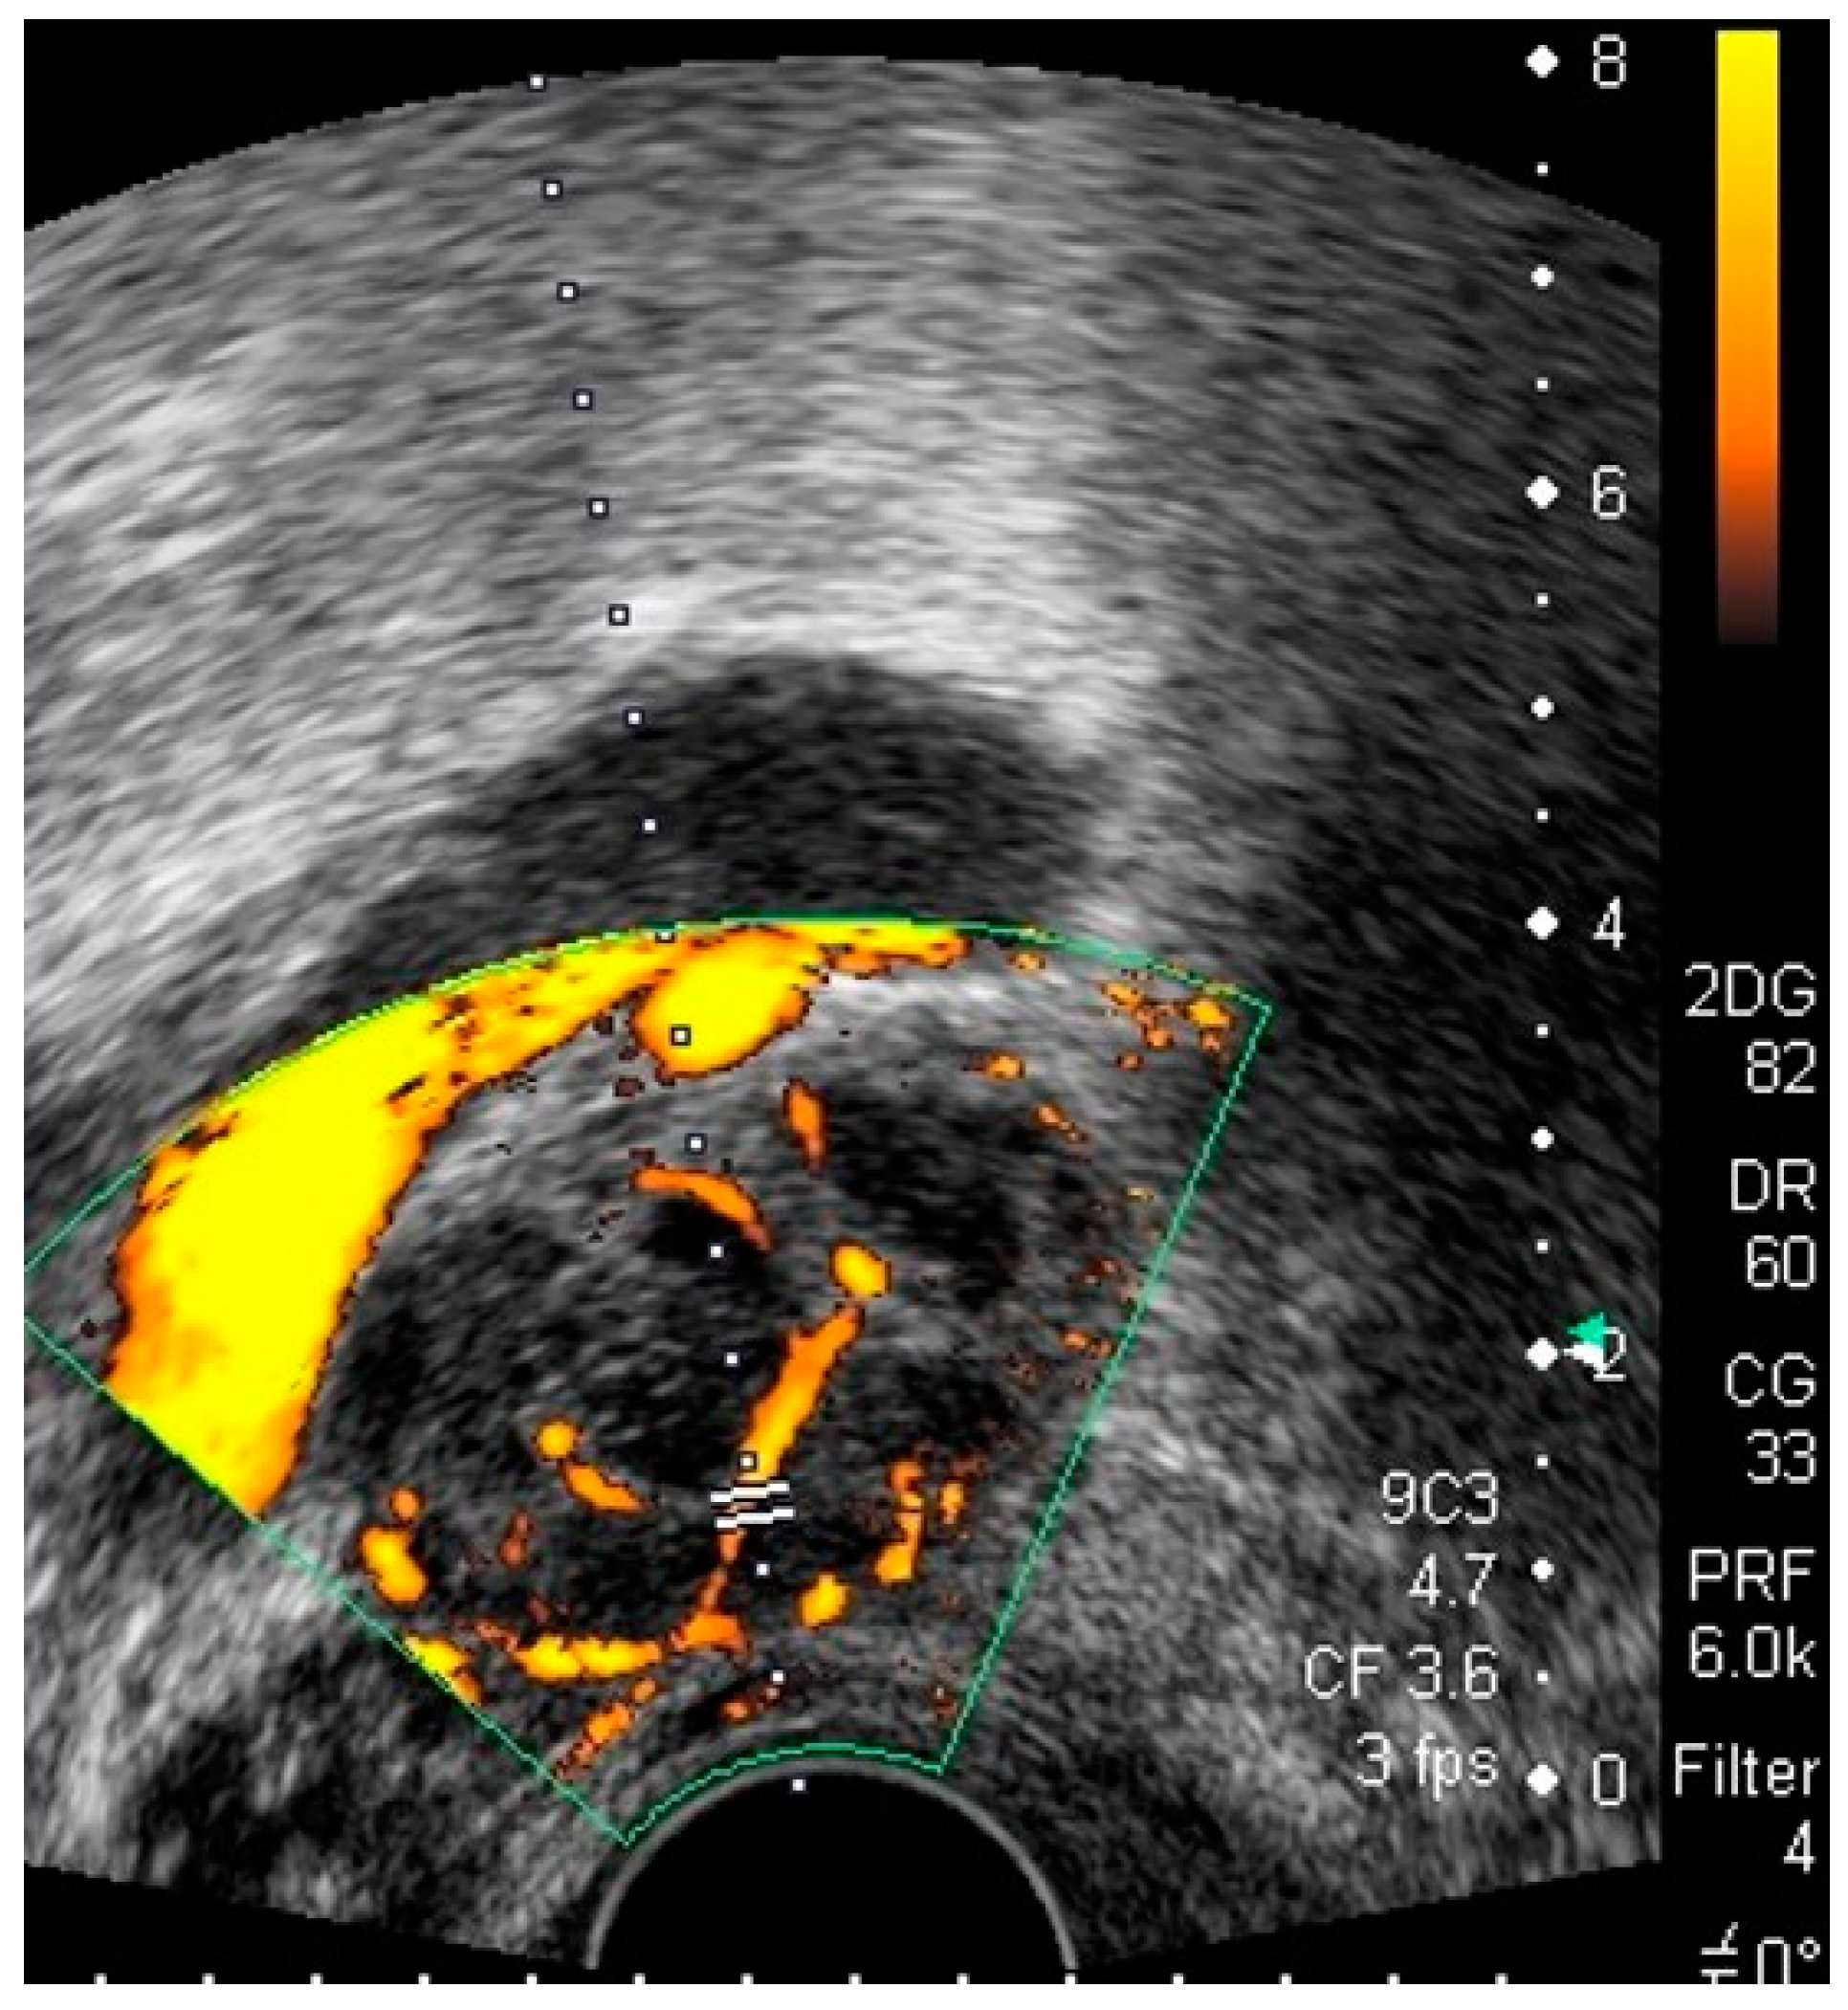

4.1. Pelvic Congestion